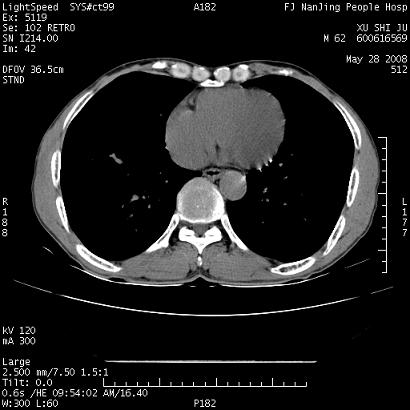

以下是引用杀毒软件在2008-5-28 19:16:00的发言:[br]病灶旁“晕轮征”,考虑肺真菌病

以下是引用qiushi在2008-5-28 20:01:00的发言:[br]空洞周围环状磨玻璃影(日晕征),考虑肺曲霉菌病.

以下是引用clj20在2008-5-28 20:50:00的发言:[br]鉴别诊断:癌性空洞壁结节。建议变换体位ct透视.[br][br]

以下是引用yuhongjun在2008-5-29 4:28:00的发言:[br]空洞周围环状磨玻璃影(日晕征),考虑肺曲霉菌病。支持! [br] [br]

以下是引用lrj在2008-5-28 21:10:00的发言:[br]所示应该是正常结构,是对称的,多个层面都有!也不像是内乳动脉或是肿大淋巴结![br]右下肺渗出性病变伴空洞形成,其洞内见一结节,以下诊断都有可能:1 右下肺曲菌感染, 2右下肺结核空洞形成伴曲菌感染!3右下肺结核空洞伴壁内占位形成,虽说后者发生的几率很低 但作为我们应该多考虑一下吧!最重要的结合临床